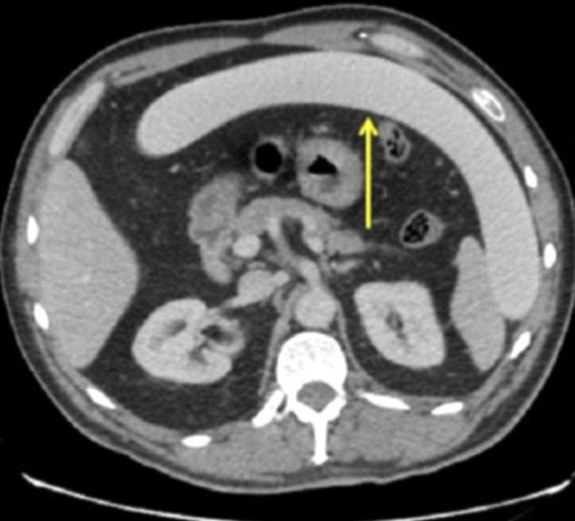

Şiddetli ağrıları olan hasta, Yorkshire bölgesinde bulunan bir hastanenin acil servisine başvurdu. 53 yaşındaki adam hastaneye geldiğinde oldukça sarhoştu. Sarhoş olduğu için oyuncağın kontrolünü kaybettiği öğrenilen adamın içinde sıkışan nesne, çekilen röntgende açık bir şekilde görüntülendi.

Nesneyi cinsel zevk için kullandığı öğrenilen adamın bağırsaklarının delindiği tespit edildi. Doktorlar olayı, muazzam boyutları sebebiyle türünün ilk örneği olarak nitelendirdi. Cerrahlar cinsel ilişki oyuncağını başarıyla çıkartırken, yırtılan kısım da dahil olmak üzere bağırsağın 20 cm'lik kısmı kesilmek zorunda kaldı.